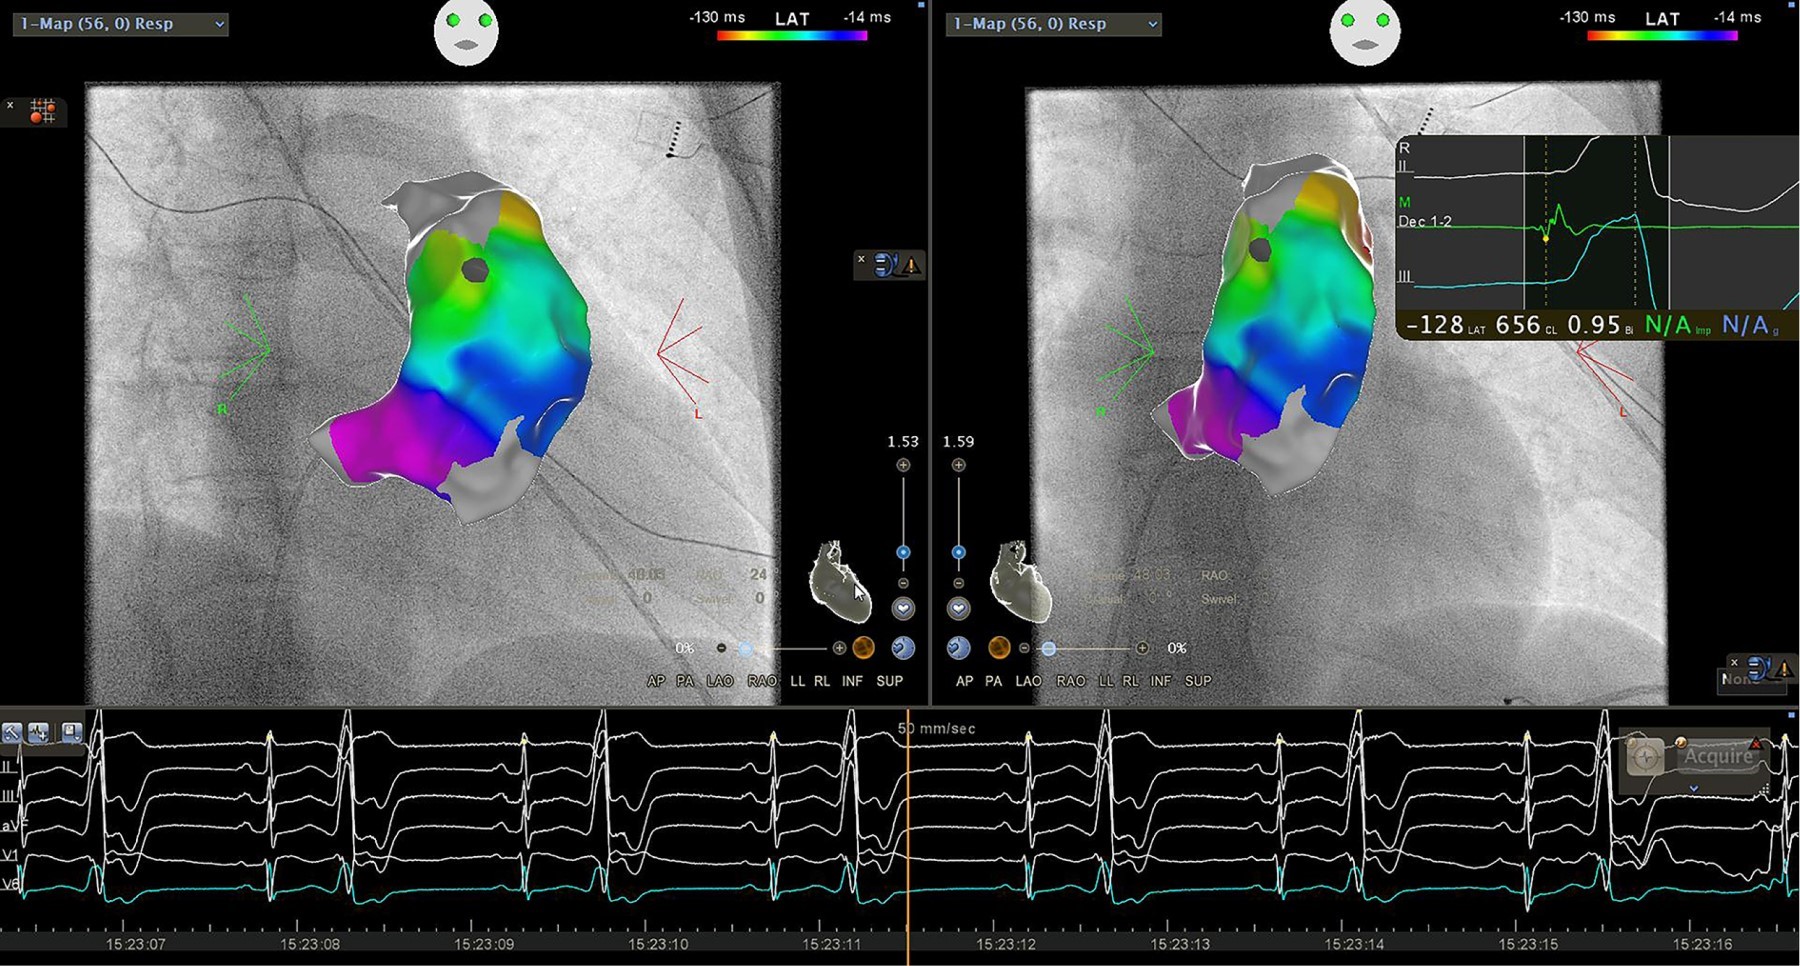

Reducción de la exposición a la radiación en un laboratorio de electrofisiología con el módulo CARTO-UNIVU™

La ablación por radiofrecuencia es una técnica eficaz y segura para el tratamiento de diferentes tipos de arritmias. La ablación por radiofrecuencia se realiza mediante fluoroscopia, una guía de navegación estándar, que está asociada con la exposición a la radiación y sus efectos nocivos bien reconocidos para los pacientes y para el personal de laboratorio. En la última década, los sistemas de mapeo electroanatómico han experimentado un fuerte desarrollo. A pesar de sus indiscutibles ventajas, no incluyen información obtenida por fluoroscopia en tiempo real. El módulo CARTO-UNIVU™ aborda esta importante limitación, ya que combina imágenes de fluoroscopia con el mapeo eletroanatómico tridimensional (3D) en una sola vista 3D, lo que permite una reducción pronunciada de la exposición a la radiación. Presentamos cuatro casos de nuestra primera experiencia en un solo centro con el nuevo módulo CARTO-UNIVU™.

Figura 2